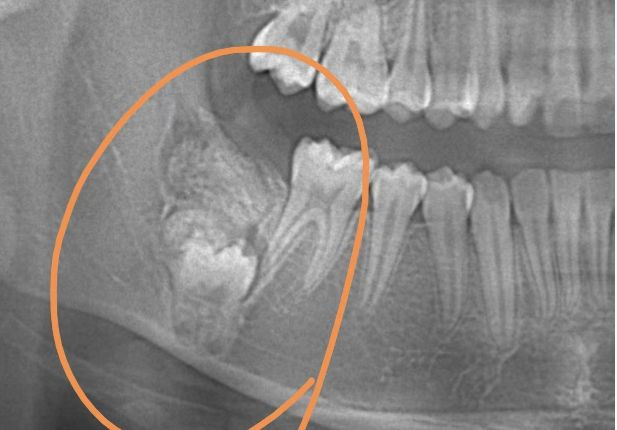

| Chụp X quang, bác sĩ đã phát hiện có một tổn thương giống như khối u ở hàm dưới bên phải của bé gái 12 tuổi. |

Theo thông tin đăng tải, Tiểu Nhã, 12 tuổi, ở Thượng Hải, Trung Quốc, đến bệnh viện để điều trị chỉnh nha vì hàm răng khấp khểnh. Thật bất ngờ, trong lúc chụp X quang, bác sĩ phát hiện có một tổn thương giống như khối u ở hàm dưới bên phải của Tiểu Nhã khiến chiếc răng này không thể mọc ra bình thường.